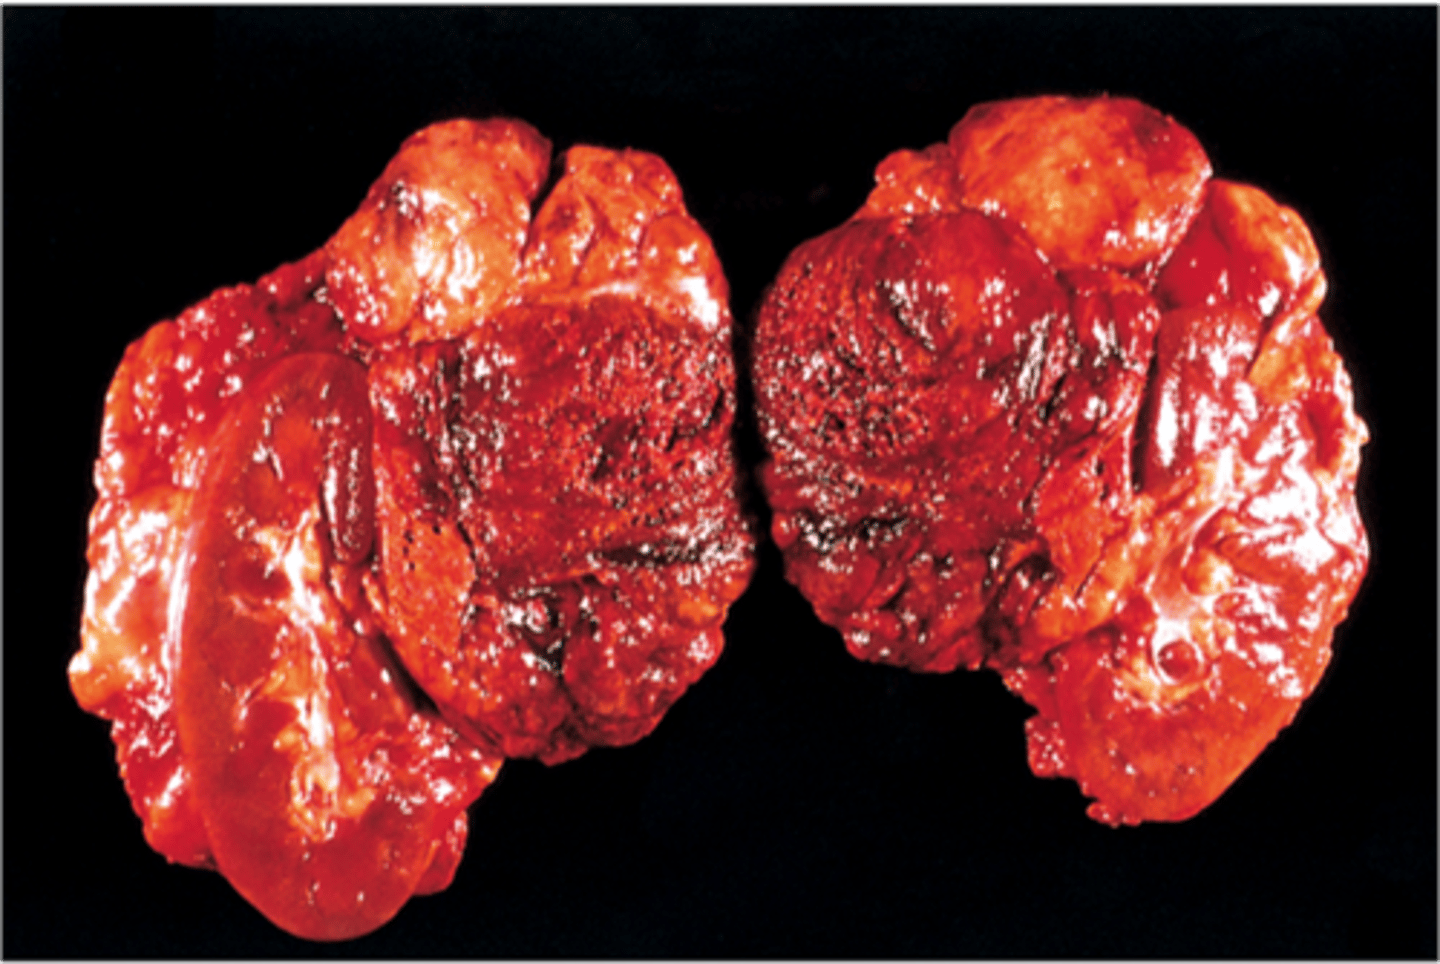

adrenal carcinoma

Pathology?